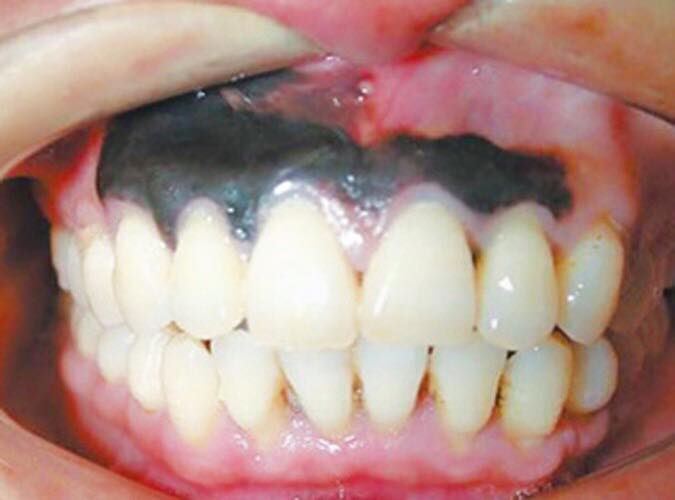

4.Vùng nướu sưng, đổi màu bất thường

Khi bị bệnh ung thư hoặc bệnh răng miệng thường quan sát thấy một số dấu hiệu bất thường nướu thay đổi màu, đỏ thẩm đậm màu hơn, đồng thời quan sát còn thấy một số dấu hiệu kèm theo đó là hơi thở có mùi hôi, chảy máu, chảy mủ dịch trắng ở vùng chân răng…